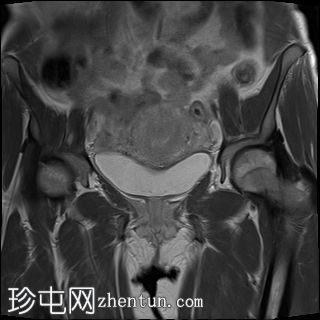

冠状位

T2加权像

左侧卵巢增大、水肿,位置异常,卵泡呈周边排列

左侧卵巢血管扭转,呈漩涡征

左侧卵巢实质出血性改变

上述左侧卵巢增大、水肿、位置异常、卵泡呈周边排列、实质出血的特征提示卵巢扭转伴出血。梗死。

患者被转诊至妇科医生处,并紧急行输卵管卵巢切除术。病理检查显示广泛的出血性梗死,卵巢包膜下仅残留薄薄一层完整组织。未发现恶性肿瘤